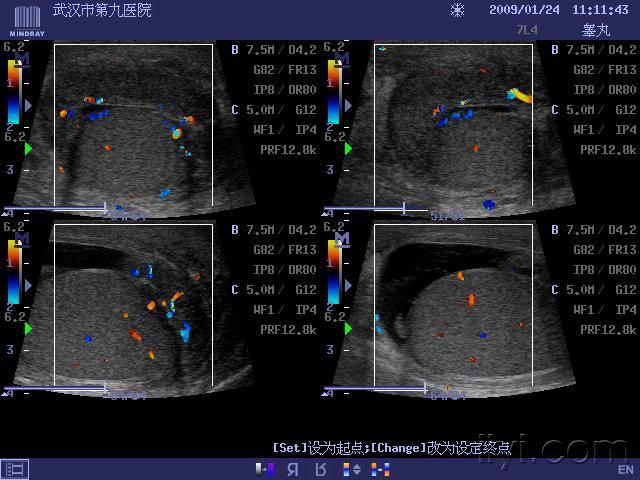

一组附睾尾炎性体积肿大的图片

图片尺寸640x480

附睾肿大明显,血流信号丰富.

图片尺寸600x450